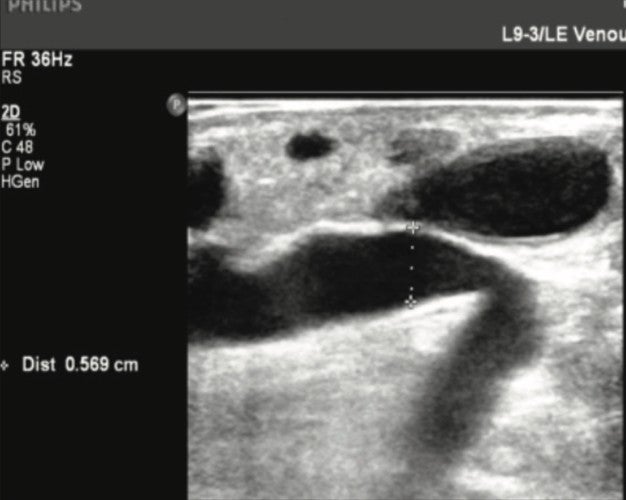

Figure 1. Thigh GSV Tributary pre-Varithena treatment.

The left Great Saphenous Vein (GSV) had a large refluxing branch from the groin level which measured 23.2mm at the groin and 20.4mm at the mid-distal thigh where it rejoined the GSV.

Reflux was 3.2 seconds at the groin and 4.7 seconds at the proximal-mid thigh.